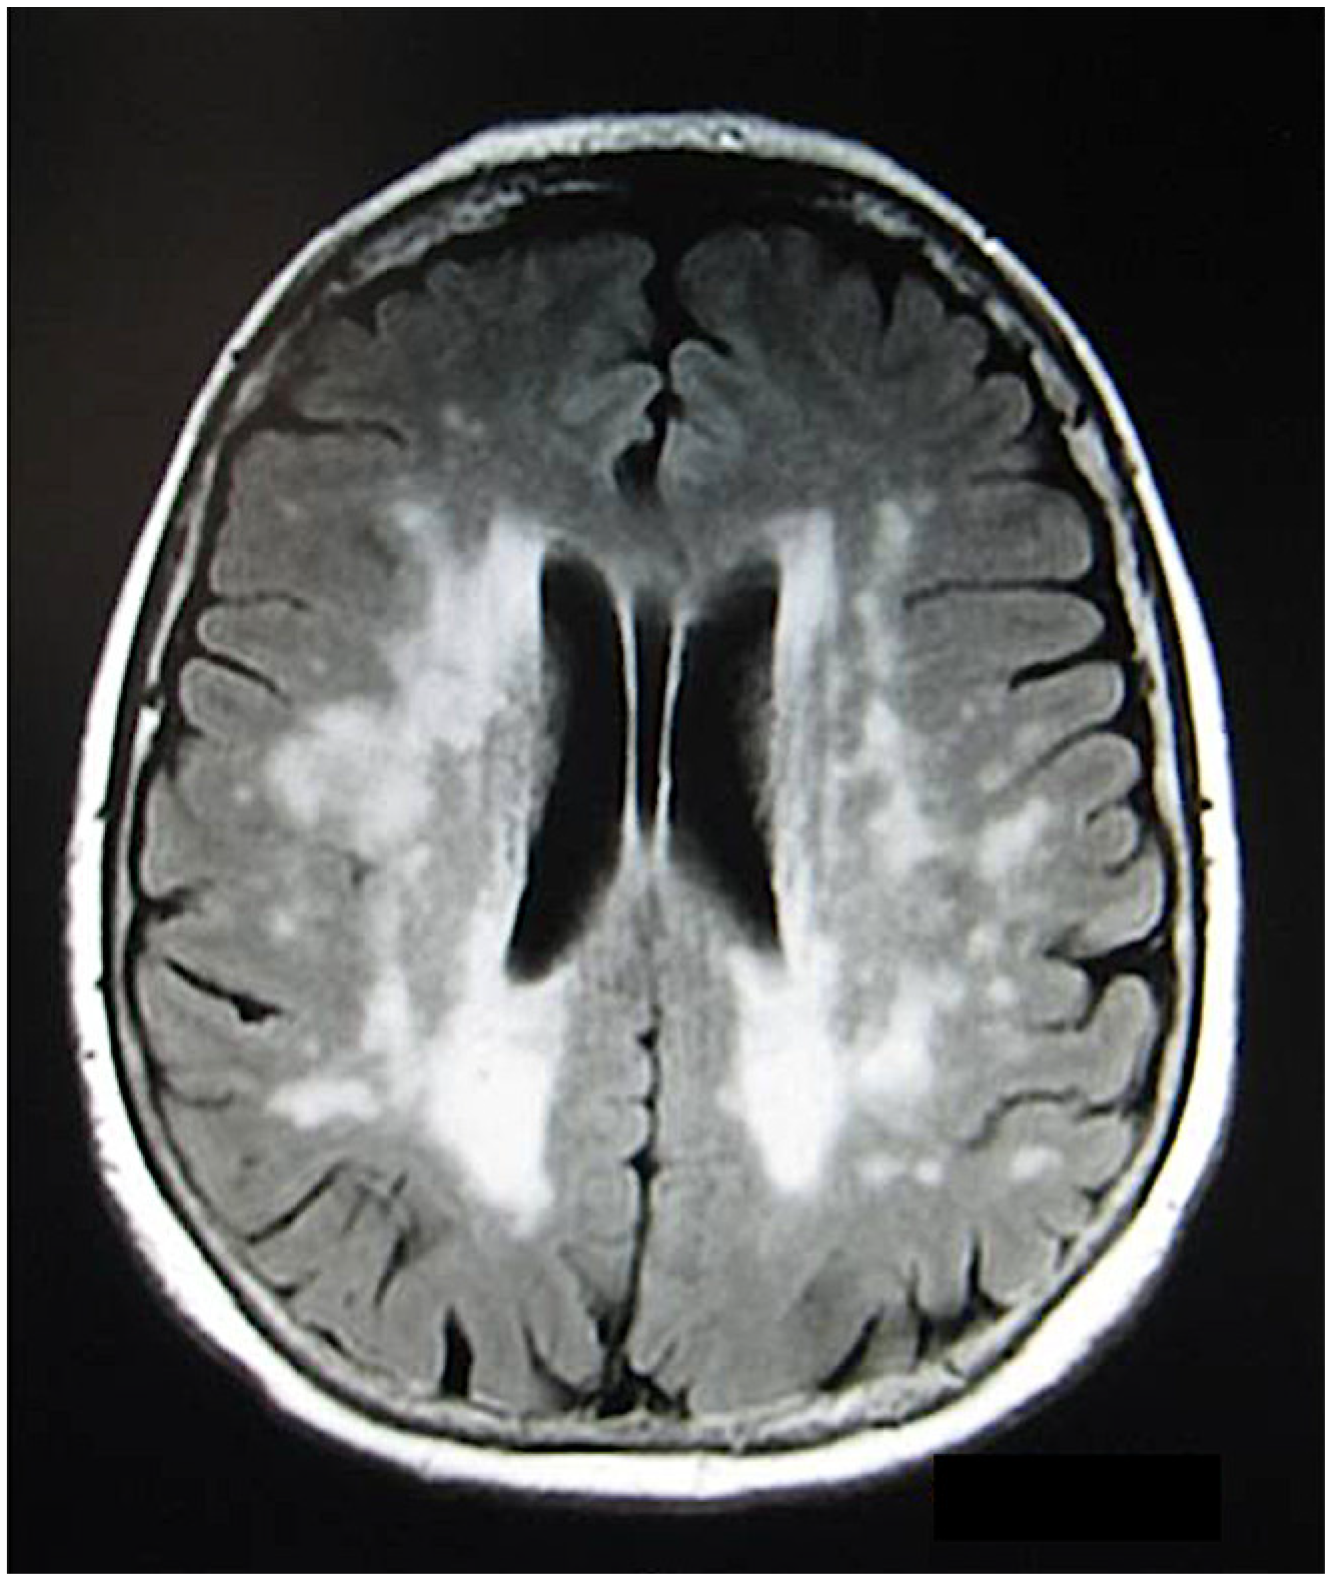

- Bradshaw, M.J.; Pawate, S.; Koth, L.L.; Cho, T.A.; Gelfand, J.M. Neurosarcoidosis Pathophysiology, Diagnosis, and Treatment. Neurol. Neuroimmunol. Neuroinflamm. 2021, 8, e1084. [Google Scholar] [CrossRef]

- Ginat, D.T.; Dhillon, G.; Almast, J. Magnetic resonance imaging of neurosarcoidosis. J. Clin. Imaging Sci. 2011, 1, 15. [Google Scholar]

- Shah, R.; Roberson, G.H.; Cure, J.K. Correlation of MR Imaging Findings and Clinical Manifestations in Neurosarcoidosis. Am. J. Neuroradiol. 2009, 30, 953–961. [Google Scholar] [CrossRef]